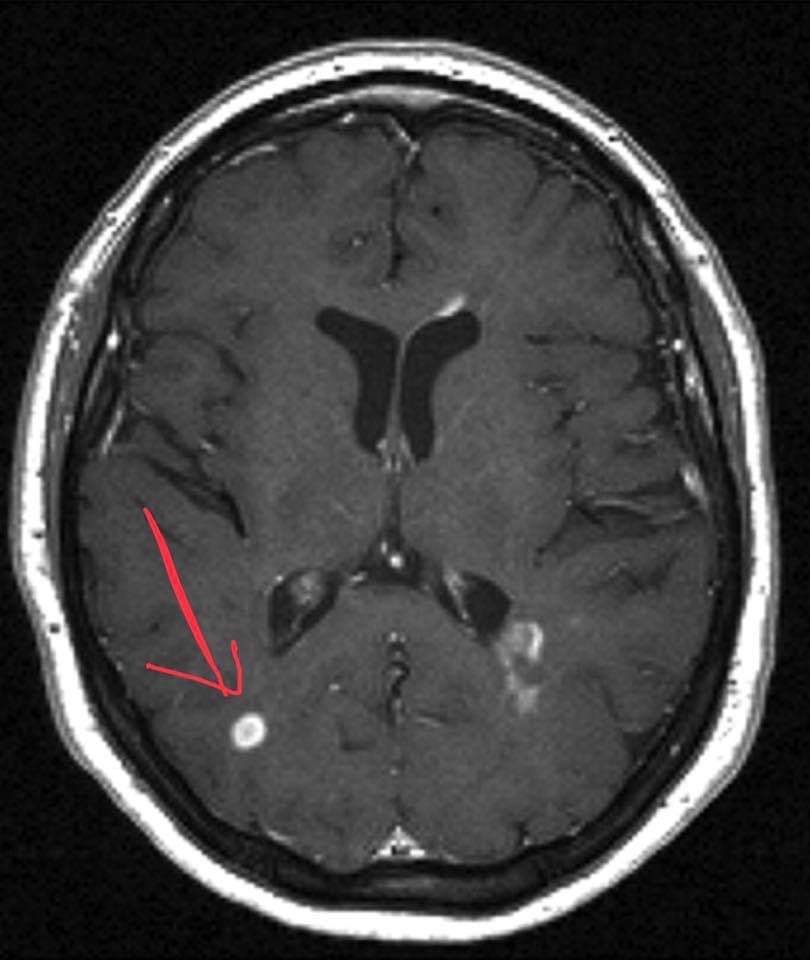

التصوير بالرنين المغناطيسي لتشخيص التصلب المتعدد

حيث يمكن أن يكشف عن مناطق التصلب العصبي المتعدد في الدماغ والحبل الشوكي.

ولدى معظم الأشخاص الذين يعانون التصلب المتعدد متكرر الإنتكاس، التشخيص يكون واضحًا إلى حد ما، واستنادًا إلى نمط الأعراض التي تتفق مع المرض والتي يتم تأكيدها عن طريق فحوصات التصوير بالدماغ، مثل التصوير بالرنين المغناطيسي.